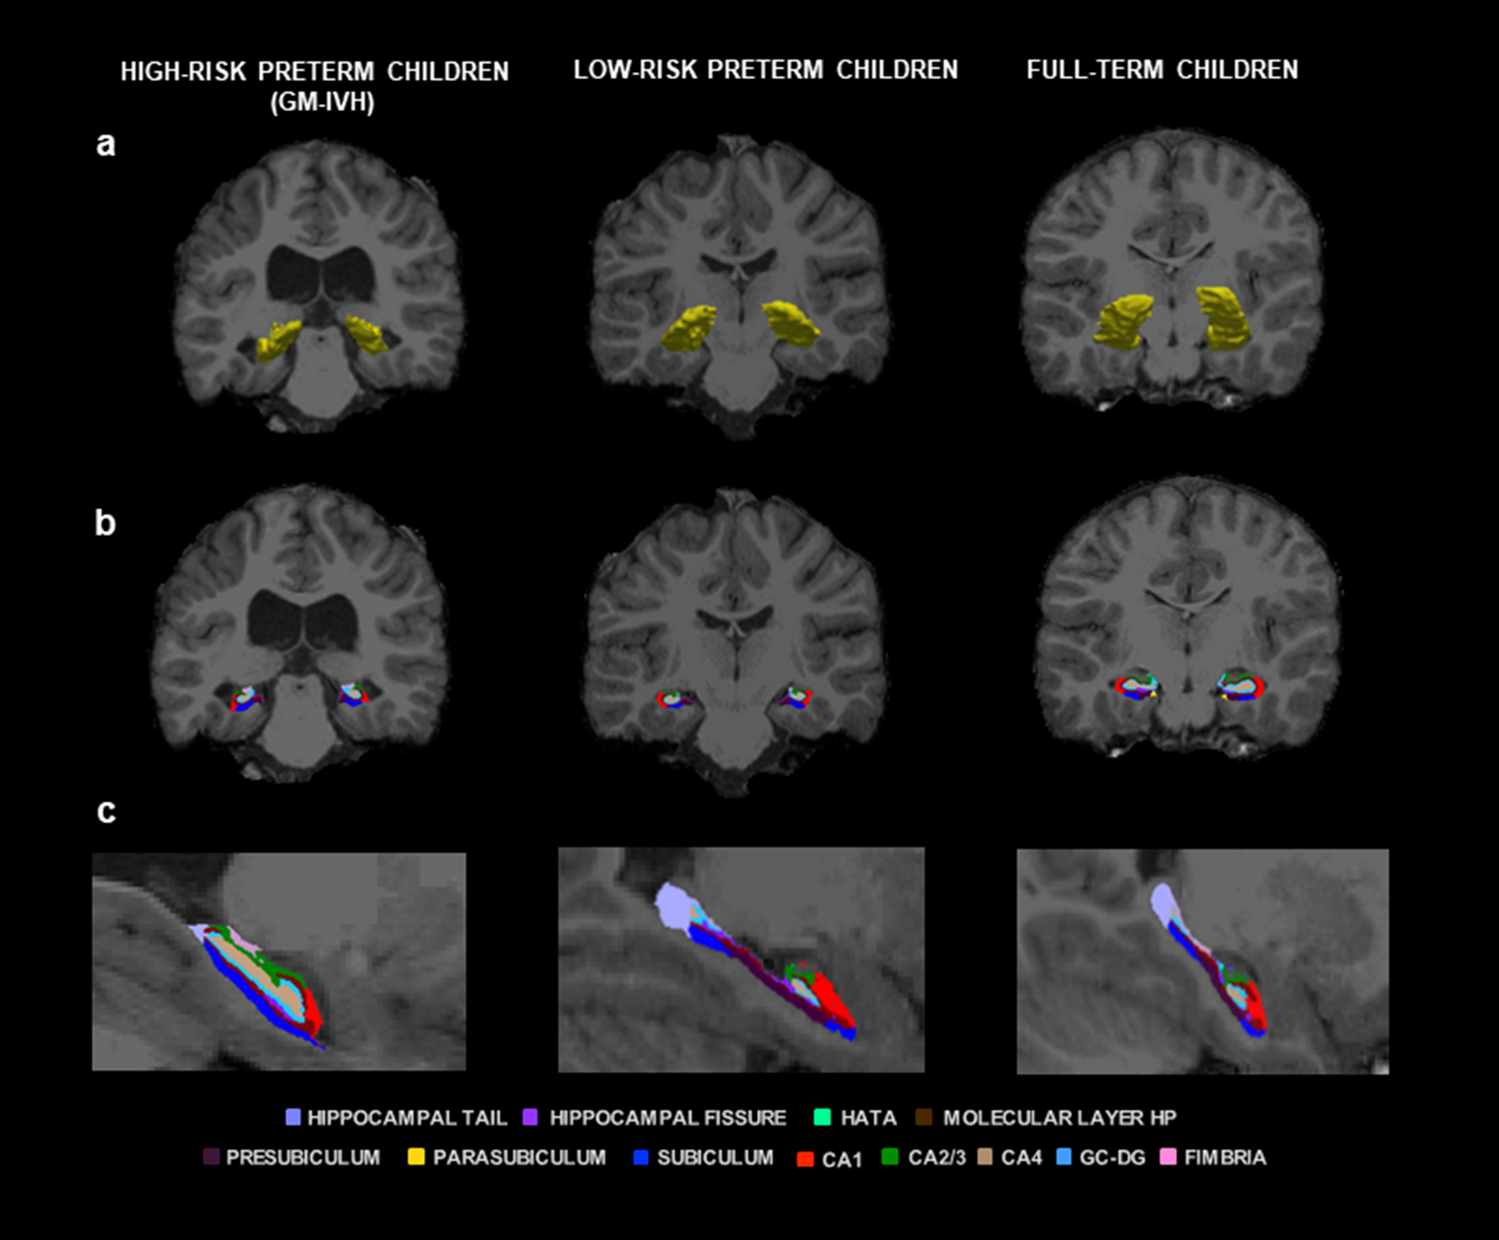

Figure 2

Right and left hippocampus and hippocampal subfield volumes. Coronal (a,b) and sagittal (c) views showing volumetric segmentation among groups in right and left hippocampus and hippocampal subfields. In accordance with radiological convention, the left side is shown on the right of the image for each view. CA: Cornu Ammonis, GC–DG: granule cell layer of dentate gyrus, HATA: hippocampal-amygdalar transition area; HP: hippocampus; and GM-IVH: germinal matrix-intraventricular hemorrhage. Coronal coordinate (a,b): x: -205.43, y: -11.00, z: -127.00; and sagittal coordinate (c): x: 2.50, y: 140.00, z: -50.05.